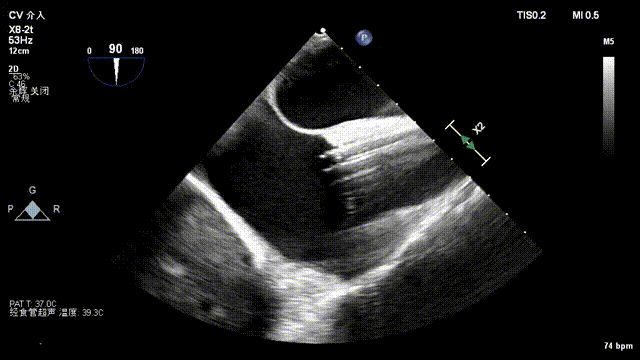

After general anesthesia, the patient underwent jugular vein puncture to establish access. An 18Fr delivery sheath was advanced over a super-stiff guidewire to the mid-to-lower right atrium. Under ultrasound guidance, the delivery system was introduced. A 14T K-Clip® and a 16T K-Clip® device were implanted at the postero-septal commissure annulus and the antero-posterior commissure annulus, respectively. The angle between the device and the annular plane was adjusted through controlled flexion and rotation to orient the device tip toward the target site. Using ultrasound MPR mode, the anchor component was advanced into the annulus. After traction confirmed stability, the clip arms were opened and apposed to the annulus. The anchor component was then retracted to close the clip arms, achieving annuloplasty. The effect was evaluated as satisfactory, and the clip components were deployed.

Advancing anchor component under MPR view

Opening clip arms, adjusting orientation, and apposing to the annulus

Closing the clip and evaluating effect under ultrasound